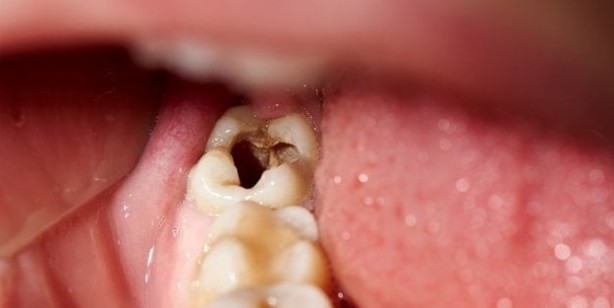

Peki bunu nasıl yapıyor? Diş köküne bir takım uyarı sinyalleri gönderen aspirin, diş yenilenme özelliğini aktif ederek bozuk dişleri onarma, sağlam dişleri ise daha sağlıklı hale getiriyor.

Dişlerin Yenilenmesinde Büyük Rol Oynuyor! Genelde diş çürümesinde kullanılan tedavi bellidir çürük çok ilerlememişse dolgu yapılır, çürük ileri seviyedeyse kanal tedavisi ile diş kurtarılmaya çalışılır. Diş kanal tedavisi ile de kurtarılmıyorsa dişin çekilmesi gibi bir durum ortaya çıkabilir. Prof. Ikhlas El Karim, Queen’s Üniversitesinde yaptığı araştırmalar ile kendinden sıkça söz ettiriyor. Biyomedikal bilimler başkanı olan El Karim, aspirinin diş dolgusu yerini alabilecek bir yapıda olduğunu bu konudaki araştırma sonucunda dolgu olmadan dişleri eski sağlığına döndürebilmenin mümkün olduğundan söz ediyor.

Diş kökünde bulunan hücreleri arttırabilmek dişin çürük dokusunun eski haline gelmesini sağlıyor ve aspirin bu noktada diş kökünde bulunan hücrelerin çoğalması için çok etkili öneme sahip. Anladığımız üzere, aspirin hücre yenilenmesinde etkili peki baş ağrımıza iyi gelmesinin sebeplerinden biri de hücreleri yeniliyor olması olabilir mi? Aspirin diş sağlığı endüstrisi hakkında çok ciddi tasarrufları da beraberinde getirebilir. Profesör El Karim, eczacılar ile ortak yapacakları çalışma ile bu tedaviyi daha hızlı bir şekilde hayata geçireceğine inanıyor. Gelecekte aspirin dolgunun yerini alır mı ya da dolgu diye bir teknoloji kalır mı bunu hep beraber göreceğiz.